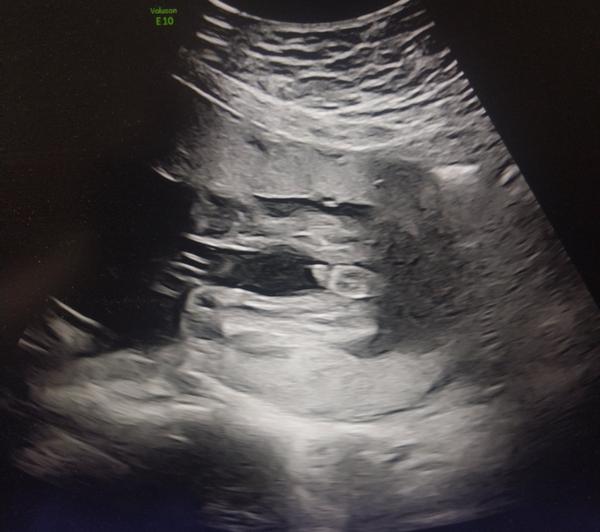

Podla fotky je to jasny chlapec.. A ked ti to lekar potvrdil... ak potrebujes "na beton" istotu, daj si zobrat krv a dat urcit pohlavie z tvojej krvi...

@chrobak7 ano to uz riesi nifty napr tie rozne microdeletions a pod. Ale vacsinou na usg byva tiez iny znak, ze nieco neni ok. Ako tu mame na obrazku jasne genitalie chlapceka. Tam naozaj jedine keby ide o nieco neodhalitelne, tak veci mozu byt inak. Ale z foto je jasne, ze mozu kupit vybavicku pre chlapca